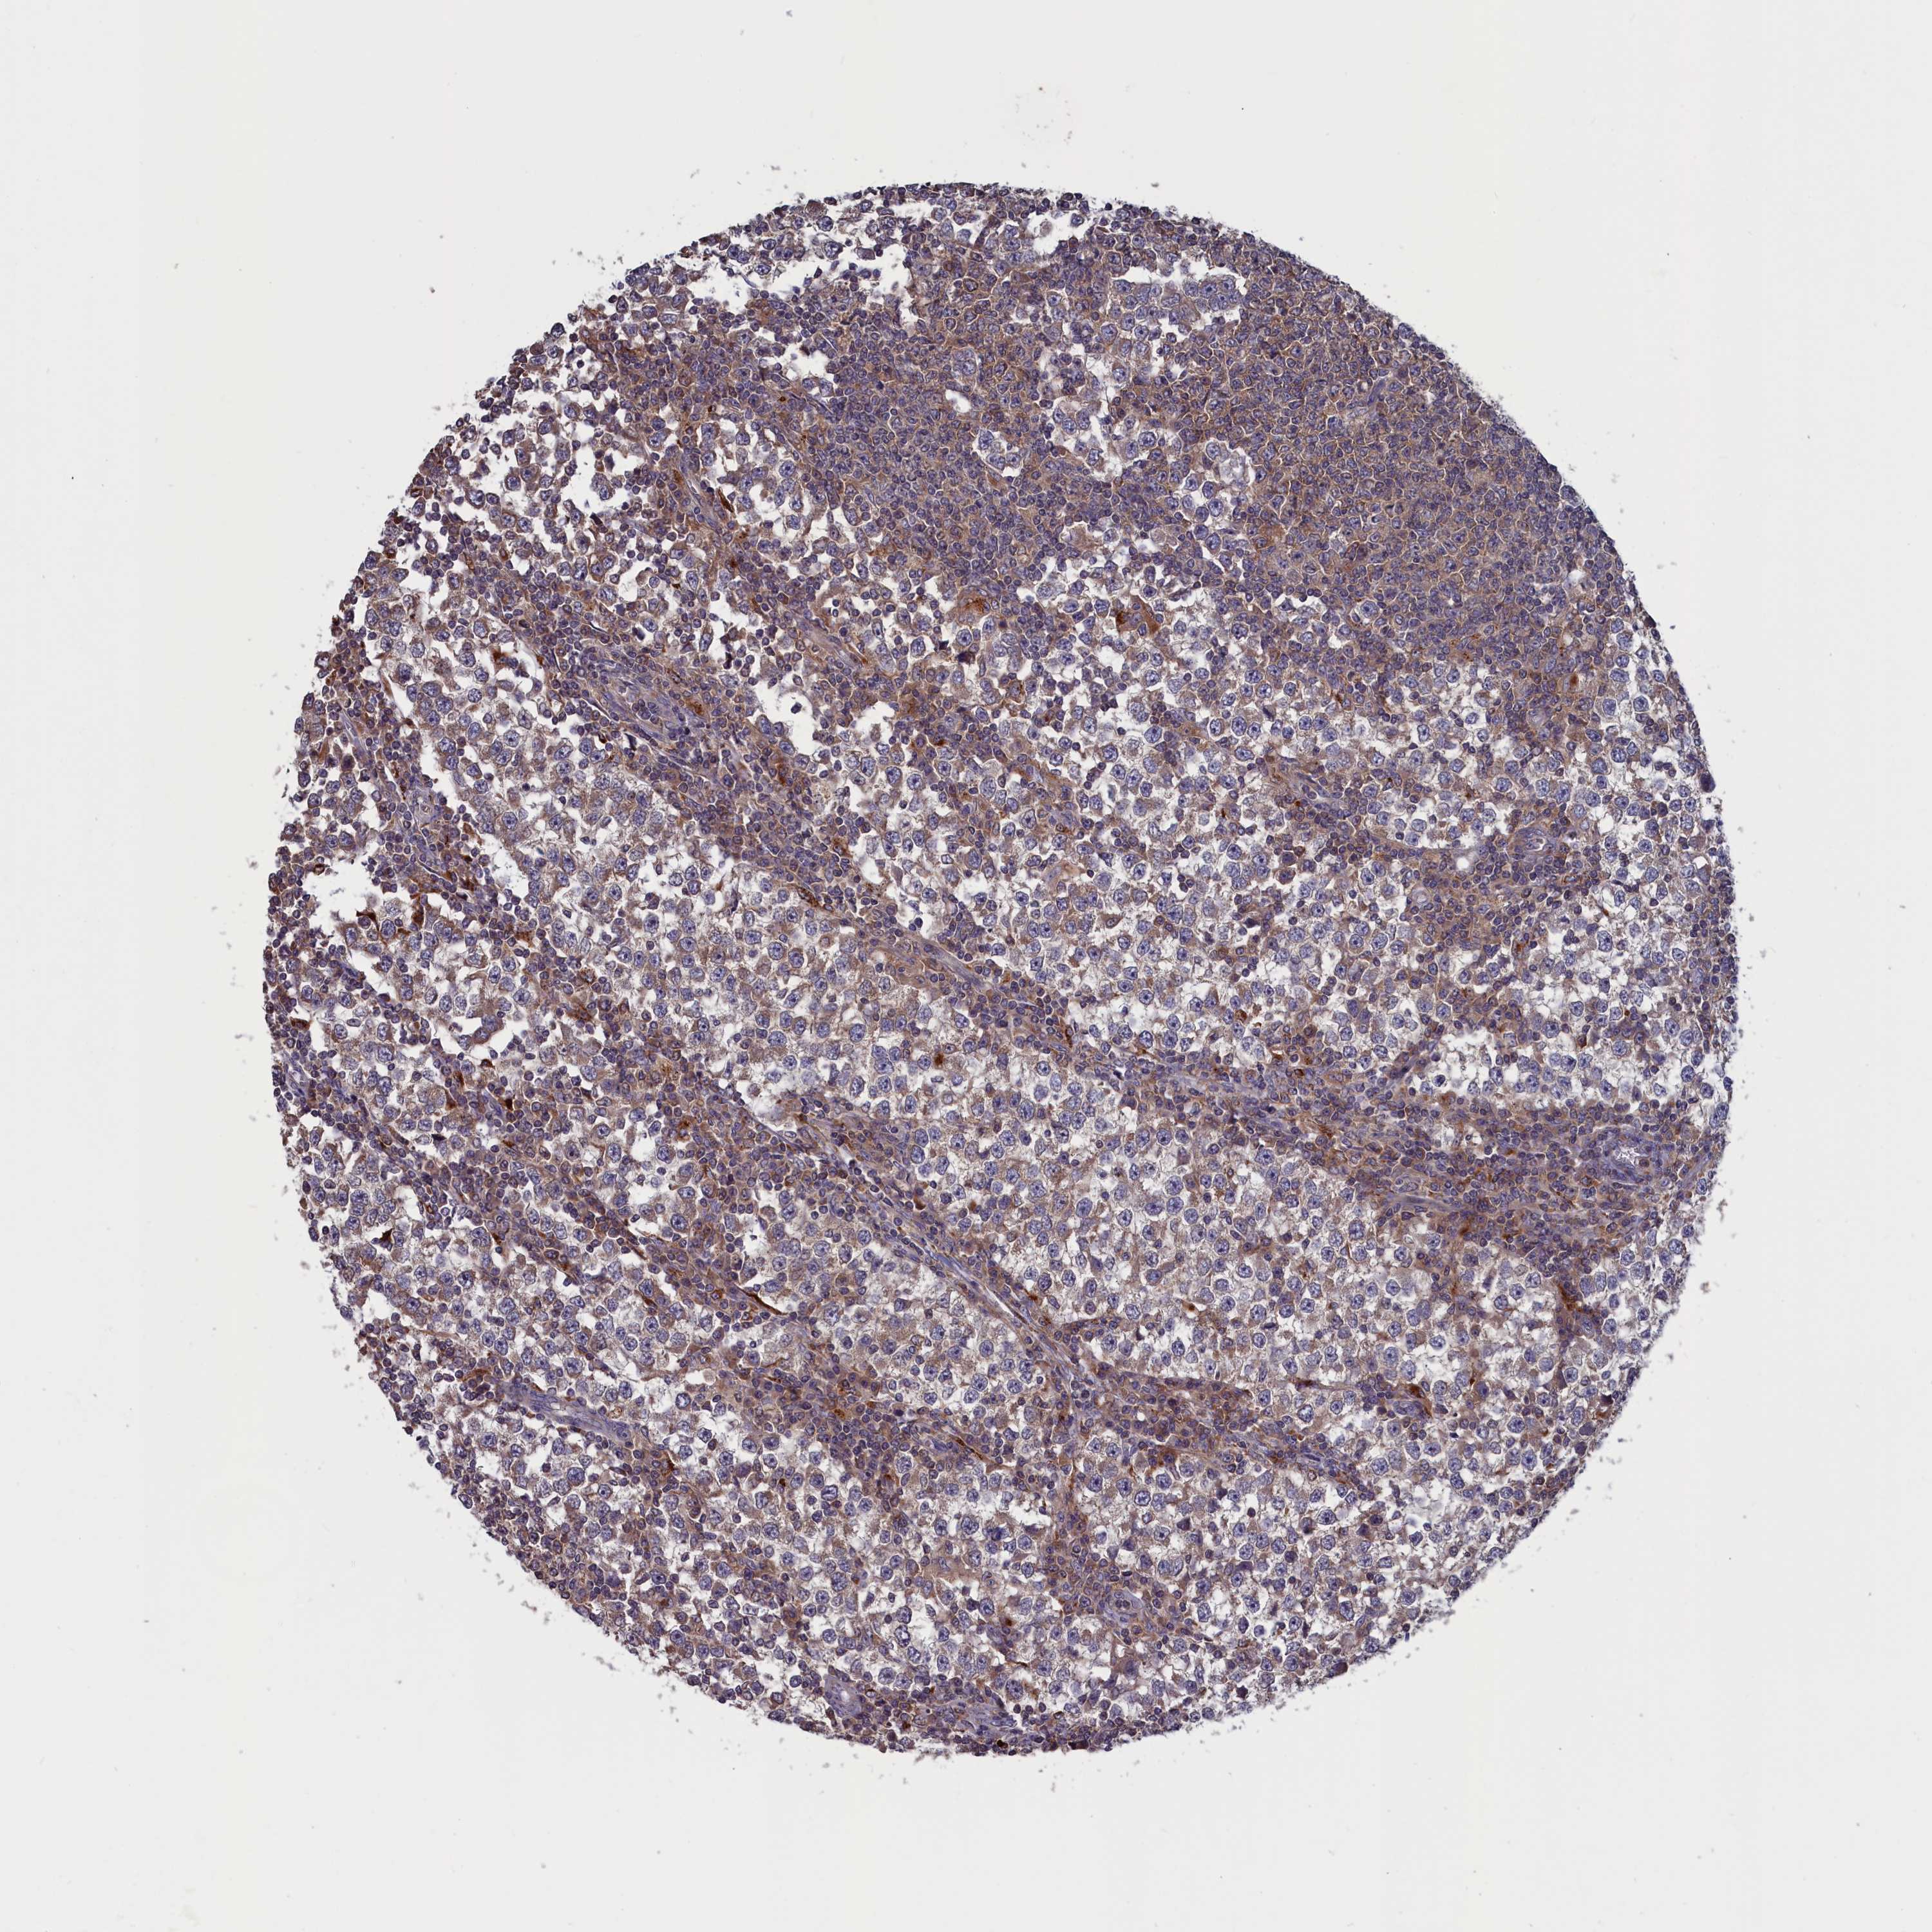

TESTIS CANCER - Protein expressioni

A mouse-over function shows sample information and annotation data. Click on an image to view it in a full screen mode. Samples can be filtered based on level of antibody staining by selecting one or several of the following categories: high, medium, low and not detected. The assay and annotation is described here.

Note that samples used for immunohistochemistry by the Human Protein Atlas do not correspond to samples in the TCGA dataset.

Antibody stainingi

Antibody staining in the annotated cell types in the current human tissue is reported as not detected, low, medium, or high, based on conventional immunohistochemistry profiling in selected tissues. This score is based on the combination of the staining intensity and fraction of stained cells.

Each image is clickable and will lead to virtual microscopy that enables deeper exploration of all samples and also displays staining intensity scores, fraction scores and subcellular localization as well as patient and tissue information for each sample.

Antibody HPA042548

Seminoma, NOS

Carcinoma, Embryonal, NOS